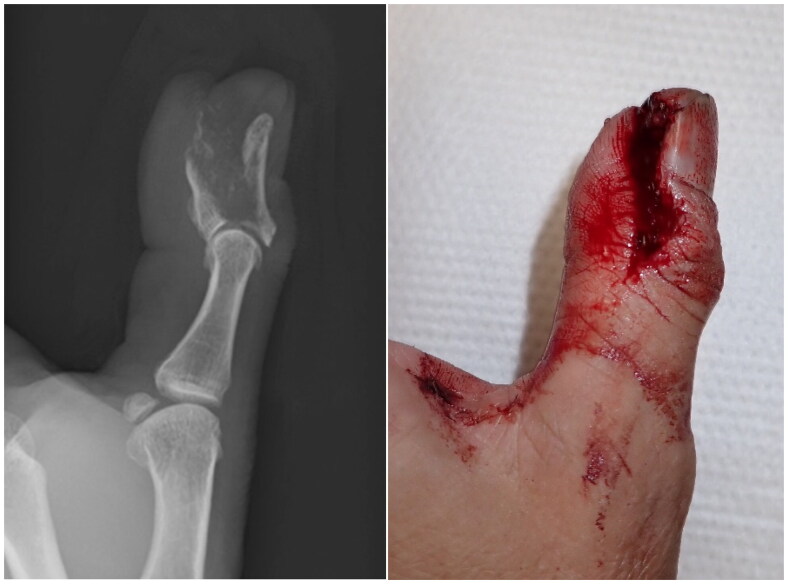

A distal phalanx may fracture in an atypical shape after high-energy trauma. A 61-year-old man sustained an open fracture of the distal phalanx of his left thumb while using a power saw. The fracture occurred in the coronal plane and the volar bone fragment was dislocated under traction by the flexor pollicis longus tendon. The patient underwent surgery the day after the injury. A flexion block pin was inserted to reduce the volar bone fragment, and an external flexion force was applied using a dorsal splint to compress the dorsal bone fragment into the volar bone fragment. The pin was removed 6 weeks postoperatively, and active range of motion exercises were started 8 weeks postoperatively. Bone union was achieved with good alignment, and although the interphalangeal joint remained slightly restricted in range of motion, the patient returned to his previous job and was satisfied with the function of the left thumb.

高能创伤后远端指骨可能以非典型形状骨折。一名61岁男子在使用电锯时左手拇指远端指骨开放性骨折。骨折发生在冠状面,掌侧骨碎片在拇长屈肌腱牵引下脱位。病人在受伤后的第二天接受了手术。插入屈曲块销以复位掌侧骨碎片,并使用背侧夹板施加外部屈曲力将背侧骨碎片压缩到掌侧骨碎片中。术后6周取下固定针,术后8周开始活动范围训练。骨愈合,对准良好,虽然指间关节的活动范围仍有轻微限制,但患者恢复了原来的工作,并对左手拇指的功能感到满意。